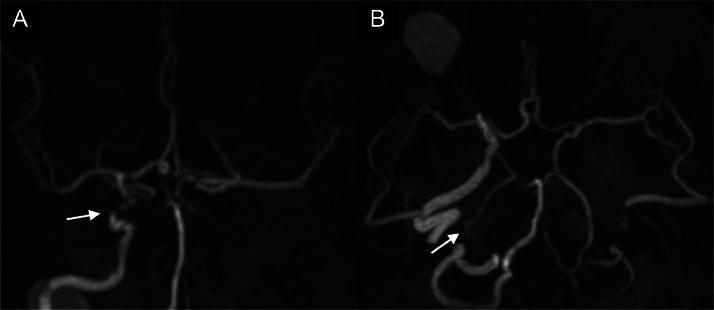

The choroid plexus is the secretory tissue responsible for cerebrospinal fluid production in the brain. Ischemia of the choroid plexus is rare because of its abundant blood supply from multiple arterial systems, including the anterior and posterior choroidal arterial anastomoses. It is not clear under what circumstances isolated choroid plexus infarction occurs. A 56-year-old woman presented to our hospital after experiencing several episodes of paroxysmal dizziness and weakness in her right upper extremity that lasted several hours. She had a 10-year history of hypertension, diabetes mellitus, and hyperlipidemia, which were very poorly controlled. Magnetic resonance imaging confirmed isolated right choroid plexus infarction. Magnetic resonance angiography showed severe stenosis of the cavernous portion of the right internal carotid artery, occlusion of the distal portion of the right posterior cerebral artery, and occlusion of the contralateral left internal carotid artery. Thus, we hypothesized that isolated choroid plexus infarction was caused by ischemia due to both atherosclerotic changes in large vessels spanning multiple vasculatures and microangiopathy around the choroid plexus due to diabetes, hypertension, and hyperlipidemia. In choroid plexus infarction, both occlusive changes in multiple large vessels and microangiopathy may be involved, and the underlying cause of these changes should be thoroughly investigated. Although choroid plexus infarction may not be significant neurologically, it may shed light on further pathogenesis in this complex structure.

脉络丛是负责在脑内产生脑脊液的分泌组织。由于其从包括脉络膜前动脉和脉络膜后动脉吻合支在内的多个动脉系统获得丰富血液供应,脉络丛缺血很少见。目前尚不清楚在何种情况下会发生孤立性脉络丛梗死。一名56岁女性因右上肢多次发作阵发性头晕和无力数小时后就诊于我院。她有10年高血压、糖尿病和高脂血症病史,病情控制很差。磁共振成像证实为孤立性右侧脉络丛梗死。磁共振血管造影显示右侧颈内动脉海绵窦段严重狭窄、右侧大脑后动脉远端闭塞以及对侧左侧颈内动脉闭塞。因此,我们推测孤立性脉络丛梗死是由于跨越多个脉管系统的大血管动脉粥样硬化改变以及糖尿病、高血压和高脂血症导致的脉络丛周围微血管病变引起的缺血所致。在脉络丛梗死中,多个大血管的闭塞性改变和微血管病变可能均有涉及,应对这些改变的潜在原因进行深入研究。虽然脉络丛梗死在神经学上可能并不显著,但它可能为这一复杂结构的进一步发病机制提供线索。